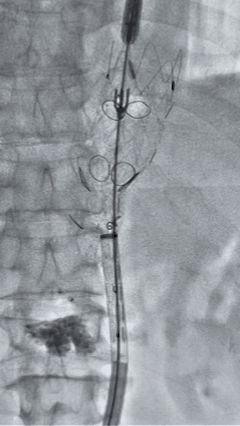

8. 从右侧股动脉入路送入腹主支架AB-24-12-110-S,近端重叠胸腹主动脉支架远端,调整好支架位置后释放。

9. 经左股动脉送入导丝导管,超选进腹主动脉支架短腿内,后沿导丝送入髂支,同理,右侧沿导丝送入髂支并释放,使用先健顺应性球囊后扩各支架连接处及支架近远端,最后通过预留导管向瘤腔注入人纤维蛋白粘合剂数支,造影显示分支通畅。

G-Branch在本例手术中展现出对扭曲解剖结构的出色适应性,针对该患者严重扭曲的瘤颈,支架系统的优异柔顺性使其能够顺利通过复杂路径,完成内脏分支血管的重建。

其独特的双内嵌、双外翻混合多分支设计兼顾了操作效率与结构可靠性,预置导丝系统简化了肠系膜上动脉(SMA)和腹腔干动脉(CA)的超选流程,显著提高手术效率。